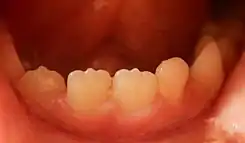

Mamelones en los incisivos inferiores centrales y laterales derechos de un niño de siete años.

Los mamelones están presentes en incisivos centrales y laterales permanentes. Los mamelones son más fáciles de observar en los dientes incisivos centrales superiores y aparecen como tres pequeñas prominencias en el borde oclusal del diente. Los mamelones generalmente no tienen importancia clínica. Por lo general, se desgastan temprano en la vida del diente. Sin embargo, cuando está presente una mordida abierta anterior, es decir, cuando los dientes no están en contacto al estar la boca completamente cerrada, los mamelones pueden permanecer en la edad adulta. [cita requerida]